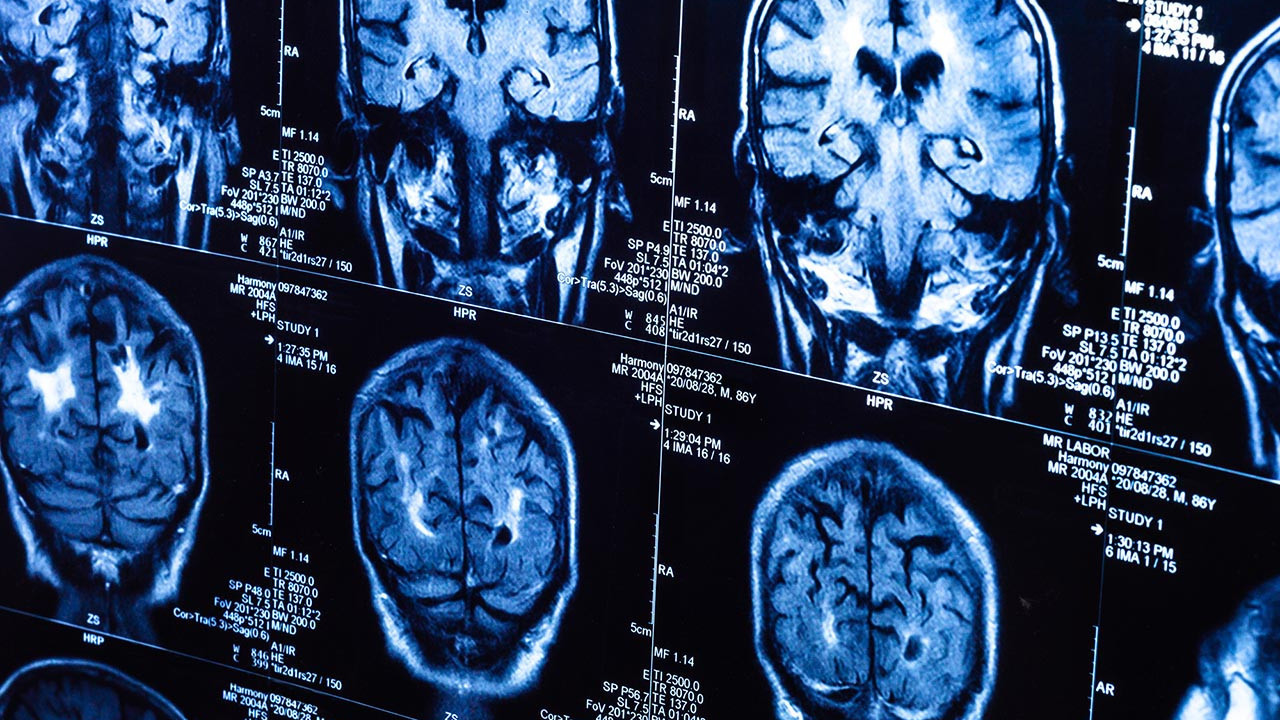

Covid-19 pandemisinin gizli etkisi 5 yıl sonra ortaya çıktı

İngiltere'den bilim insanlarının yaptığı araştırmaya göre, Covid-19 döneminde insanların beyinleri 2020 öncesine kıyasla ortalama 5,5 ay daha hızlı yaşlandı.

Nottingham Üniversitesi’nden bilim insanları, UK Biobank’ta yer alan 15 binden fazla yetişkinin verileriyle sağlıklı beyin yaşlanmasını tanıyan bir yapay zeka modeli geliştirdi. Model, pandemiden önce tarananlarla, önce ve pandemi sırasında taranan iki grubun beyin yaşlarını karşılaştırdı.

Araştırmaya göre, pandemi sürecinde insan beyninin yaşlanma hızı ortalama 5,5 ay öne çekildi.

Çalışmayı yürüten nörolog Ali-Reza Mohammadi-Nejad, “Covid geçirmeyenlerde de belirgin artış gördük. İzolasyon ve belirsizlik gibi faktörler beyin sağlığını etkiledi” dedi.

Ekipten nörolog Dorothee Auer ise verilerin iki zaman noktasına ait olduğunu belirterek, “Gördüğümüz değişikliklerin geri dönebileceğini söylemek mümkün, bu da cesaret verici. Beyin sağlığını sadece hastalıklar değil, çevremiz de şekillendiriyor” ifadelerini kullandı.